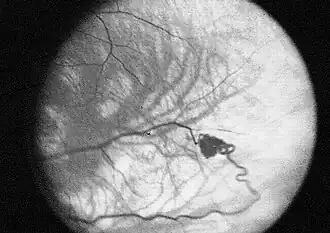

- Hemangioblastomas - tumores del sistema nervioso central (especialmente en el cerebelo, tronco del encéfalo y médula espinal). También se llaman así los que aparecen en la retina.

Eugen von Hippel fue quien primero describió los angiomas oculares (1904),[10] y Arvid Vilhelm Lindau describió los angiomas del cerebelo y la espina dorsal en 1927.[11]